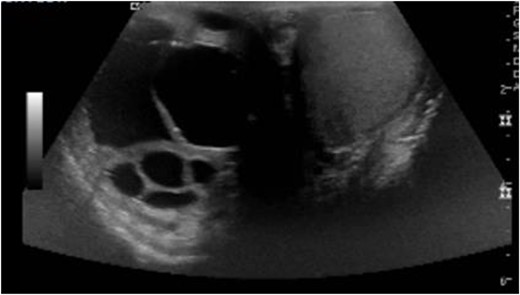

On postoperative Day 1, scrotal ultrasound was performed. The ultrasound findings were significant for a 6 cm complex cystic mass in the right scrotum (Fig. 2). Immunohistochemical analysis of the resected liver tumor showed positive reaction with pancytokeratin, HCG and SALL4 (Fig. 3A and B). Subsequent laboratory results showed an elevated b-hCG of 130, 985 mIU/ml, lactate dehydrogenase of 581 U/L and alpha fetoprotein of 2 ng/ml.